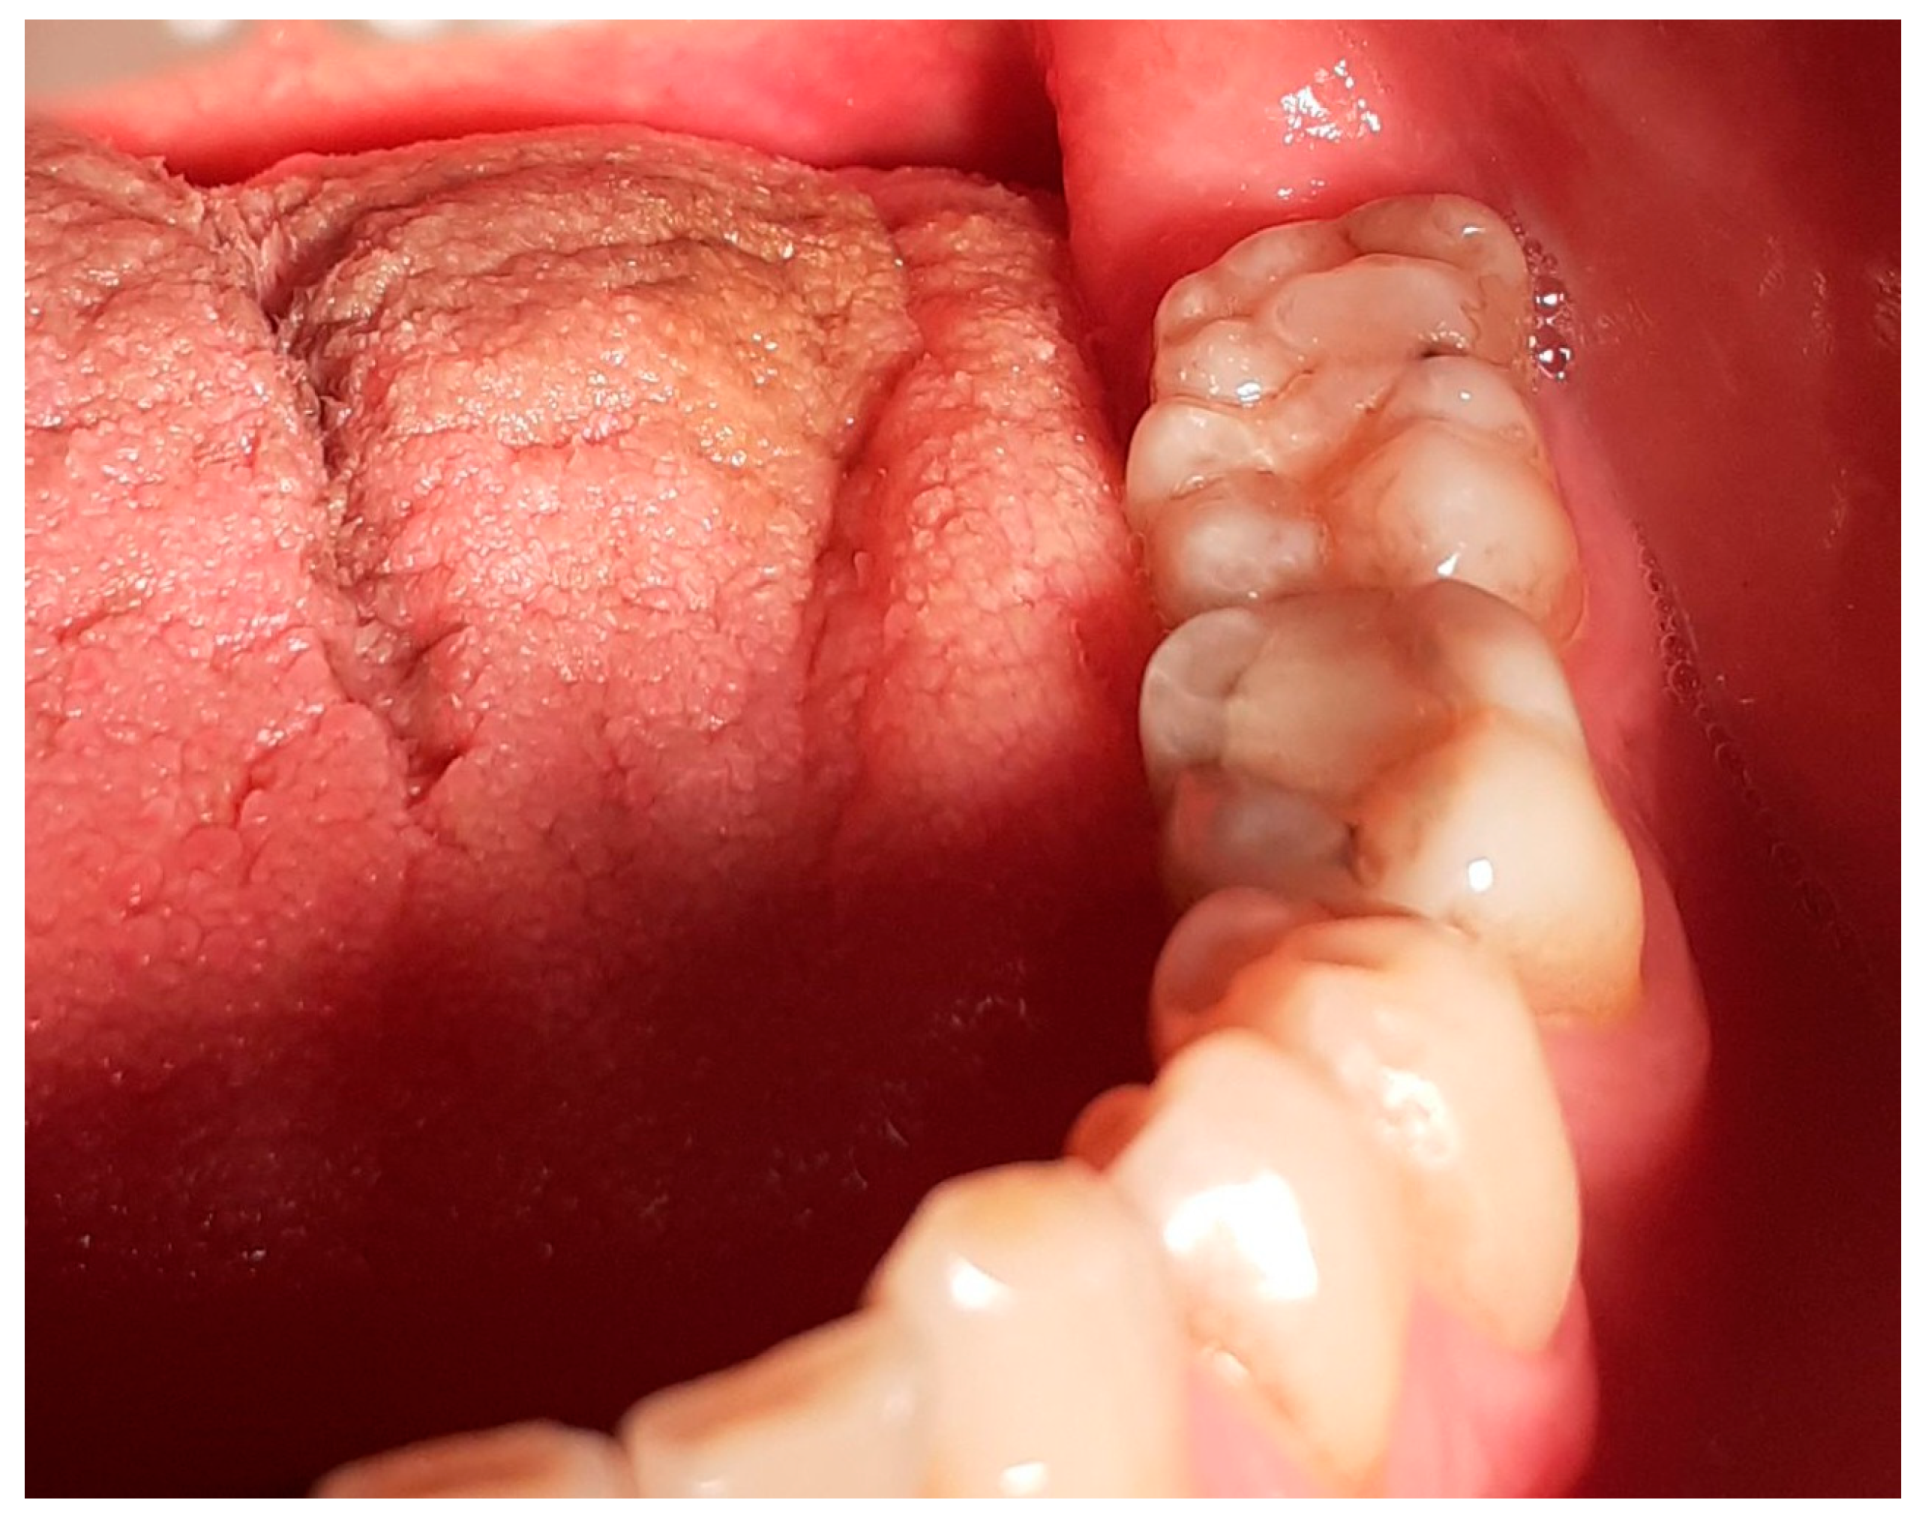

A 69-year-old Greek male patient presented in the dental office complaining about discomfort on the right maxillary area and asking for comprehensive oral treatment. During the clinical examination, a morphologically atypical molar was identified in the area of #37–38, presenting with a large crown in the mesio-distal dimension (‘double’ crown) (Figure 1). The patient reported having a panoramic radiograph taken two months ago, which revealed the internal structure of the deviating tooth, along with the neighboring teeth and bone structures. To develop the treatment plan, which included periodontal treatment, restorative procedures and fixed prosthetics, selected intraoral radiographs were additionally performed, as well as diagnostic casts (Figure 2).

Figure 1.

Intraoral photograph, left mandibular posterior area.

The crown of the atypical molar exhibited eight cusps (Figure 3). There were four buccal and four lingual cusps: the sizeable mesio-buccal cusp, middle-buccal (small-sized), disto-buccal (sizeable, located towards the middle of the occlusal surface) and the disto-buccal-angle cusp (located at the buccal–distal angle); the mesio-lingual cusp, middle-lingual, disto-lingual (small-sized) and the disto-lingual-angle cusp, which seemed to be composed from two smaller cusps, divided by a shallow fissure. The shape of the cusps was similar to the shapes of the mandibular molar cusps, and their positions in the occlusal surface also resembled the normal ones, with the exception of the buccal–distal cusp, which had a flattened ridge and a vertical bucco-lingual orientation resembling a large marginal ridge. This was the second biggest cusp in size, following the mesio-buccal cusp, which was the biggest. The fissures of the occlusal surface were deep and enhanced, and there were no signs of erosion. The atypical molar was occluded with the first and second maxillary left molars.